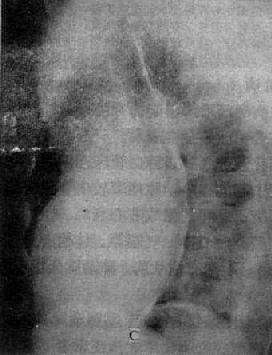

图3-2-17 慢性肺原性心脏病

心呈二尖瓣型,右心室增大,肺动脉突出,但无左心耳增大。肺动脉扩张,尤以右下肺动脉为明显,有肺门截断现象,说明有肺动脉高压。肺纹理增强,肺透明度增加,膈平而低,说明有慢性支气管炎和肺气肿